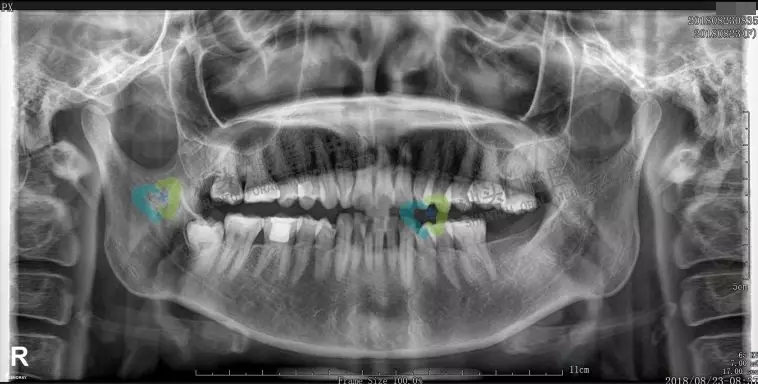

口腔全景牙片,是通过一次拍摄将全口牙齿和颌骨的影像清晰的显示在一张X光片上,可以清晰、完整的显示上颌骨、下颌骨全貌,上下颌牙列情况,牙槽骨情况,能够清晰显示上颌窦腔、窦壁、窦底情况以及颞颌关节情况,并对颌骨周围疾病的诊断提供准确有效的帮助。